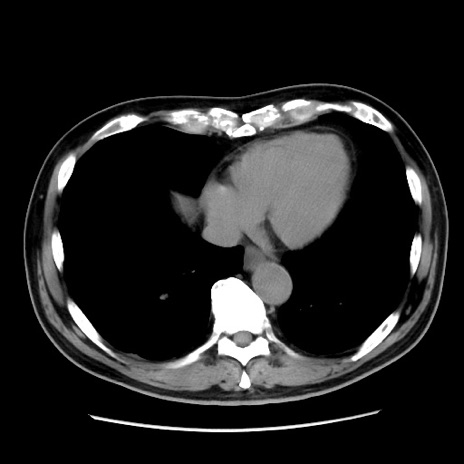

症例16(横断像)

【症例】 70歳代男性

【主訴】 腹痛、嘔吐

【現病歴】 約1ヶ月前より間欠的に腹痛と嘔吐あり、当院消化器内科を受診したところCTで多発する肝臓のLDAを指摘され、精査中であった。以降は消化器症状は安定していたが、2日前より嘔気と腹痛があり、同日より排便・排ガスが消失した。改善認めず、 本日、救急外来を受診した。

【既往歴】 大腸ポリープ切除後。

【身体所見】意識清明・会話良好、BT 36.3℃、BP 127/80mmHg、 P 80bpm、腹部:膨満あり、平坦・軟、上腹部正中および下腹部正中に圧痛あり、反跳痛なし、筋性防御なし。

【データ】WBC 7200、CRP 0.77